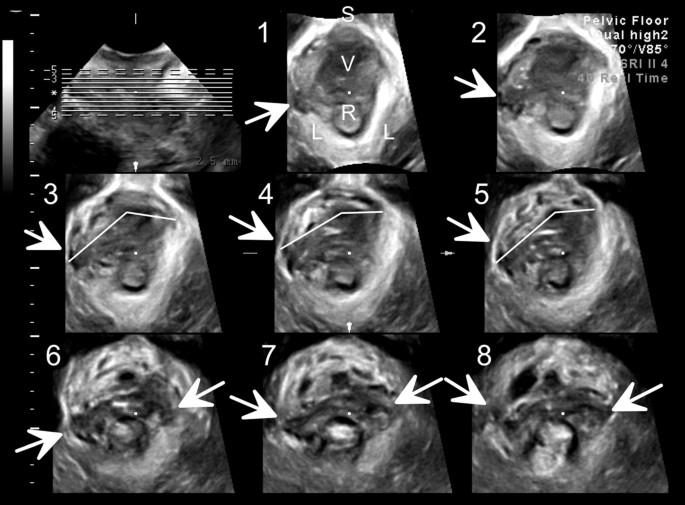

In den meisten Fällen verursacht eine Nierenvergrößerung bei einem Fötus keine offensichtlichen Symptome. Sie wird in der Regel während einer routinemäßigen Ultraschalluntersuchung während der Schwangerschaft entdeckt. Wenn die Nieren erweitert sind, kann dies auf eine Blockade oder einen abnormalen Harnabfluss hinweisen. Weitere diagnostische Tests wie eine Doppler-Ultraschalluntersuchung oder eine Magnetresonanztomographie (MRT) können durchgeführt werden, um die genaue Ursache und den Schweregrad der Erweiterung festzustellen.